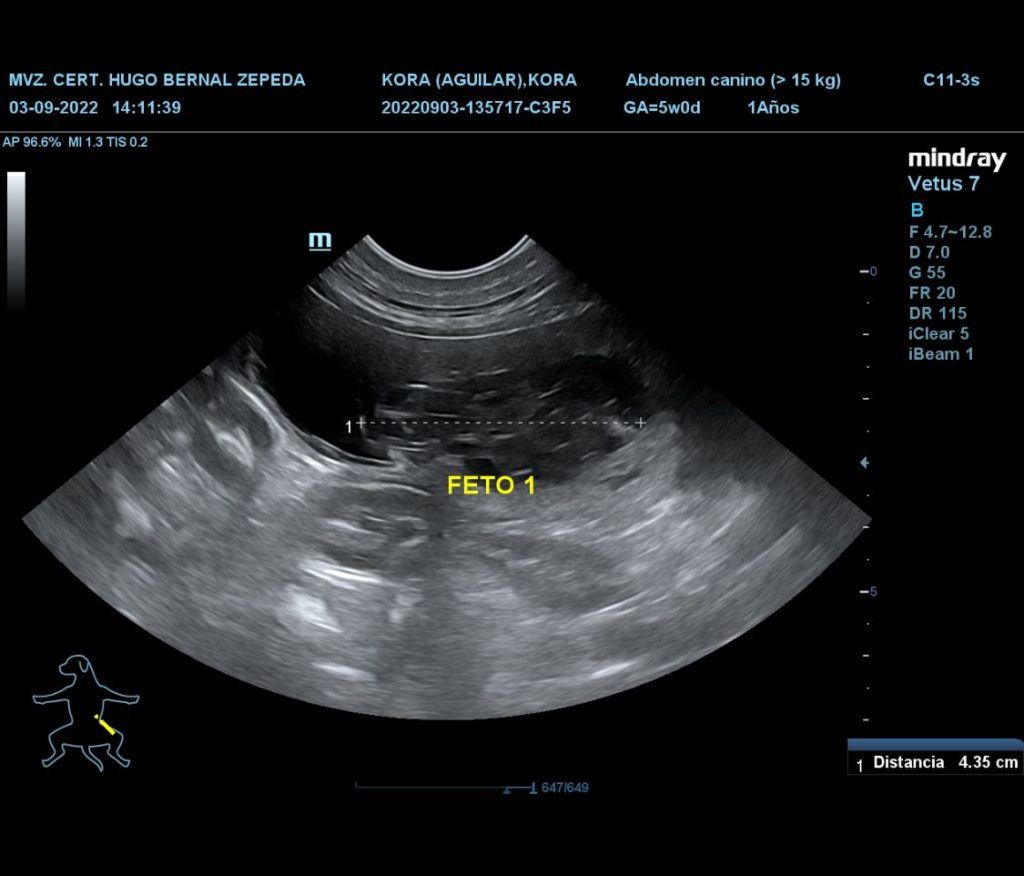

El día de hoy nos llena de dicha el informarles que la gestación de nuestra linda Kora fue confirmada por nuestro amigo y Médico Veterinario Zootecnist de cabecera Hugo Bernal Zepeda, noticia que nos ha invadido de alegría. Se estima que el nacimiento de los cachorros sea a finales del mes de Septiembre de 2020, así que muy atentos, ya que próximamente les estaremos compartiendo más detalles.